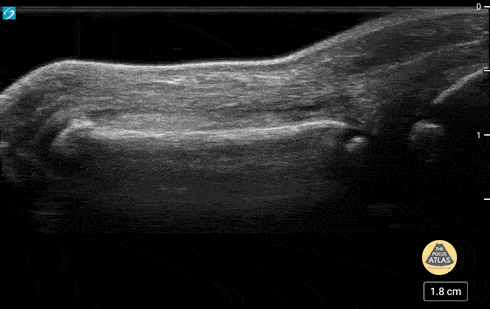

5 yo with normal finger anatomy in a waterbath. Case series 2 of 2 Contributor: Paul Khalil, MD Nicklaus Children's Hospital @khalil3paul